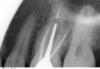

Korn05 Опубликовано 30 сентября, 2012 Поделиться Опубликовано 30 сентября, 2012 (изменено) Здравствуйте. Уже год беспокоит зуб. Так достал, что уже начинаю думать - может удалить его. История такая:1) год назад в нем были некачественно пролечены каналы в зубе, после чего он и начал постоянно и то слабо, то средне болеть 2) полгода назад каналы были перелечены якобы качественно. Зуб болеть продолжал, но боль ослабла, стало тупой. И при этом по-прежнему постоянной. Жить с ней можно, но не очень приятно.Врачи (а их было двое) на снимках этого зуба не увидели ничего негативного. Говорят, что каналы пролечены, кист нет, воспалений нет, болеть ничего не должно. На вопрос: "Почему же болит?" - разводят руками.Одной из их гипотез было то, что возможная причина боли - в давлении временной пломбы на десну и причинение ей боли, из-за чего посоветовали поставить вкладку и временную коронку и посмотреть, что будет с болью.Временная коронка стоит уже почти 2 недели. Боль, кажется, усилилась. Одна из гипотез врачей - десна заживают после вмешатальства, возможно, у вас слишком чувствительные десна - подождите, все пройдет. Но когда я совсем легонько, кончиком пальца касаюсь зуба или ем, заб начинает болеть уже сильно, ноет. Иногда затихает, а потом опять начинает. Снимок прикреплен к теме (недавний). Достаточно ли такого снимка, чтобы определить в чем проблема? Если нет, то пойду в клинику еще делать. Помогите, пожалуйста, разобраться. И отдельно еще снимок всей полости рта. Зуб, про который тут идет речь - верхняя шестерка с правой стороны (для смотрящего на снимок). Изменено 30 сентября, 2012 пользователем Korn05 Ссылка на комментарий

Korn05 Опубликовано 2 октября, 2012 Автор Поделиться Опубликовано 2 октября, 2012 (изменено) Сделали компьютерную томограмму 3Д в отдельной клинике (не в той, в которой лечусь). Врач этой клиники, просмотрев томограмму, указал на небольшое затемнение в моем зубе, который болит, и сказал что это непролеченный канал (очень тонкий и почти незаметный и идущий параллельно другому, пролеченному каналу), который нельзя было обнаружить на обычном снимке или увидеть невооруженным взглядом. И поэтому врачи из моей клиники думали, что никакого канала там нет. НО у меня уже стоит вкладка на этом зубе! И вынимать ее очень проблематично. А канал естественно сам не вылечится. Я же не могу всю жизнь с больным зубом ходить. Что делать?Здесь не могу разместить эту томограмму, потому что не знаю как (это программа, которая весит 300 с лишним мбг). Если знаете как можно разместить - подскажите, пожалуйста. Изменено 2 октября, 2012 пользователем Korn05 Ссылка на комментарий